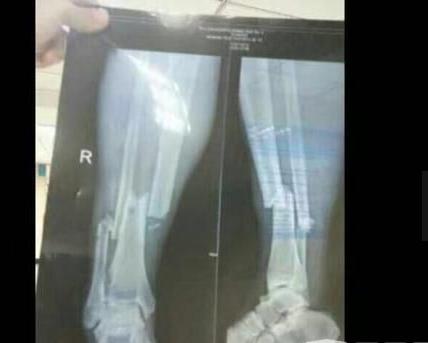

登巴巴断腿X光惨图

登巴巴断腿后1度疼的几乎晕厥,这个在赛场上就像猎豹的男人,疼的不停的哭泣呻吟。为了给他的腿复原,医生只能选择用麻醉药来让他感受不到疼痛,因为不麻醉他肯定是受不了的,甚至在整个康复期间,登巴巴也1度失望烦恼过,好在他都挺过来了。当时医生给他拍摄的X片,显示他的腿部已经粉碎性骨折非常严重,至今没有关于他腿部骨折的过多的图片视频,怕引起观众的不适感。